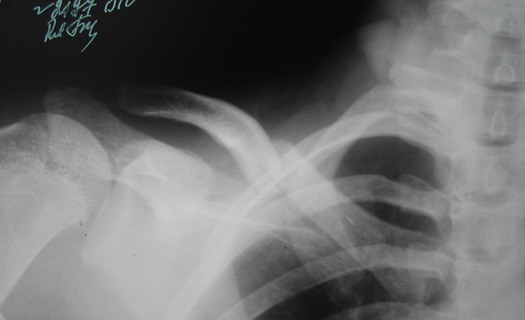

Во время стажировки в Австрии не мог не поинтересоавться, как австрийские хирурги лечат переломы ключицы. Оказалось, при переломах без смещения или с небольшим смещением накладывают восьмиобразную повязку, в остальных случаях выполняют остеосинтез пластинами.

Однако, чтобы уснуть с аппаратом внещней фиксации на ключице нужно "устать" не меньше, чем в рамке Чижина. К тому же, у некоторых больных присутсвует страх, что что-то в аппарате может раскрутиться, зацепиться за одеяло или подушку, или воспалиться. Крепко спят пациенты после качественного стабильного погружного остеосинтеза, когда ничего не торчит на коже. Особенно сладко спится после принятия душа или ванны. Это возможно после снятия швов. А вот у "чижиков" и "аппаратчиков" с полноценными водными процедурами определенные трудности.

Хотя с точки зрения кожных рубцов на видном месте, рамка Чижина и аппарат имеют явное преимущество. Но в ущерб "качеству сна"...